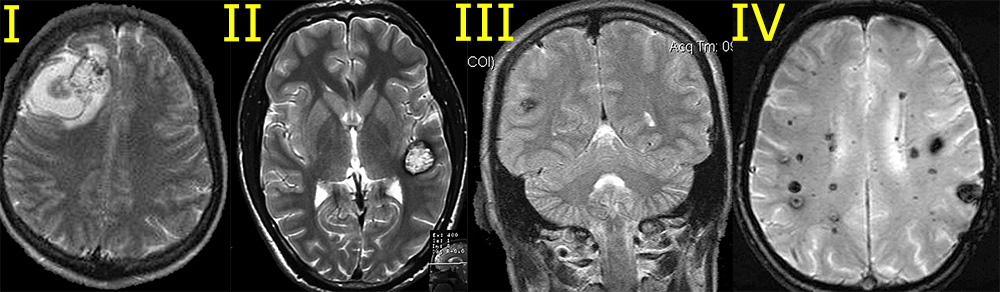

Мр картина венозной ангиомы левой гемисферы мозжечка - 96 фото